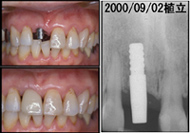

![]() 写真5■上2 顎右側中切歯部の1ピース AQBと冠の装着時(2000/09/02) |

私は歯肉縁下の形成の深さを、近遠心で0.8~1.0mm、唇側で0.6~0.8mm、口蓋側で0.3~0.4mmを標準としている。もともと支台は細いので、さらに削って細くするのではなく、必要なら少し浸麻をしてライトシャンファーまたは槍状のダイヤモンドバーを使用してインプラント周囲粘膜を形成するつもりで支台歯形成をしている。ジンパックで止血し、そこまでシリコン印象剤で印象し、Finishing Line から近遠心側と唇側でただちに歯冠部を豊隆させ、できるだけ自然に近いEemergence Profile を作ることに尽きるように思われる。また、歯肉縁下までの形成だけでは歯肉縁の Scallop形態の連続性の再現が困難なものは,歯肉切除術のようなSoft Tissue Management が必要となるが、それらにより2ピースに負けない審美性が得られる。そのような審美性の工夫を心がけて治療し経過観察をおこなっているが、大部分の症例で装着時のみならず、経年的にも審美性をほとんど損なうことなく経過している。審美性の問題はインプラントにおいてますます重要な要素になって行くのは間違いない。